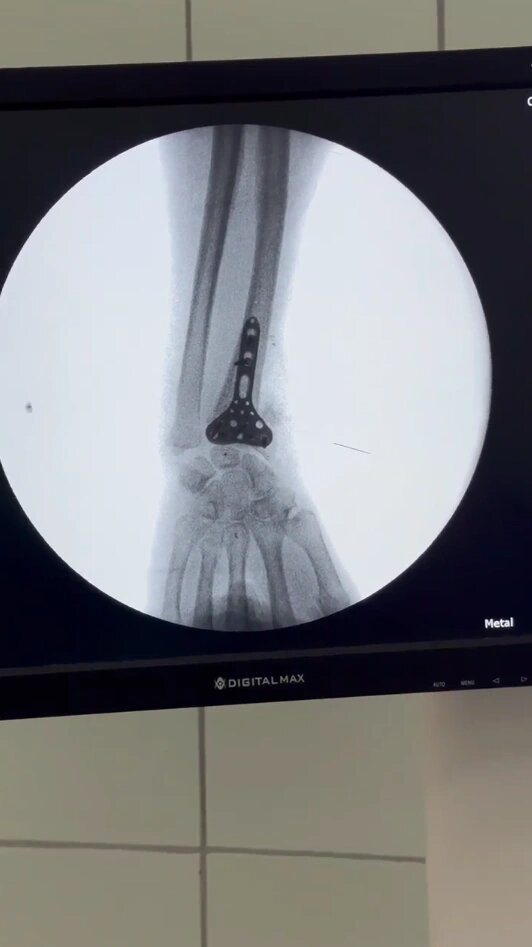

В Городской больнице скорой медицинской помощи Новочеркасска успешно провели сложную операцию. Пациентка с неправильно срастающимся переломом лучевой кости получила необходимое хирургическое лечение, которое позволит вернуть руке полноценную функцию. Пациентка получила закрытый внутрисуставной перелом в конце декабря 2025 года. После первичного вправления и наложения гипса на контрольных снимках было выявлено вторичное смещение костных отломков. В конце января 2026 года она была госпитализирована в ГБСМП для оперативного лечения. Операцию по коррекции деформации и фиксации лучевой кости титановой пластиной провели 30 января врачи-травматологи Сергей Киселев и Николай Любимов. В результате хирургического вмешательства была полностью восстановлена анатомия лучезапястного сустава, что является ключевым условием для возвращения нормальной подвижности и функции руки.

Фото: ГБУ РО "ГБСМП" в г.Новочеркасске